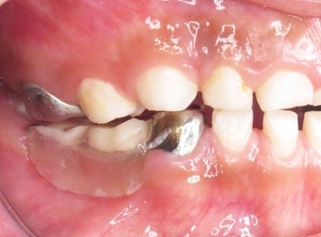

A la exploración intrabucal presentó dentición primaria incompleta, múltiples lesiones cariosas activas en molares superiores e inferiores, ausencia clínica de primer y segundo molar primario inferior derecho (Figuras 2, 3 y 4). Previo consentimiento informado, leído, explicado y firmado por tutora, se rehabilitó cavidad bucal de menor en cuatro citas diferentes mediante técnicas decir-mostrar- hacer y refuerzo positivo.

Figura 3 Fotografía oclusal inferior. Se observan lesiones cariosas activas en molares inferiores lado izquierdo y ausencia clínica de molares lado derecho.